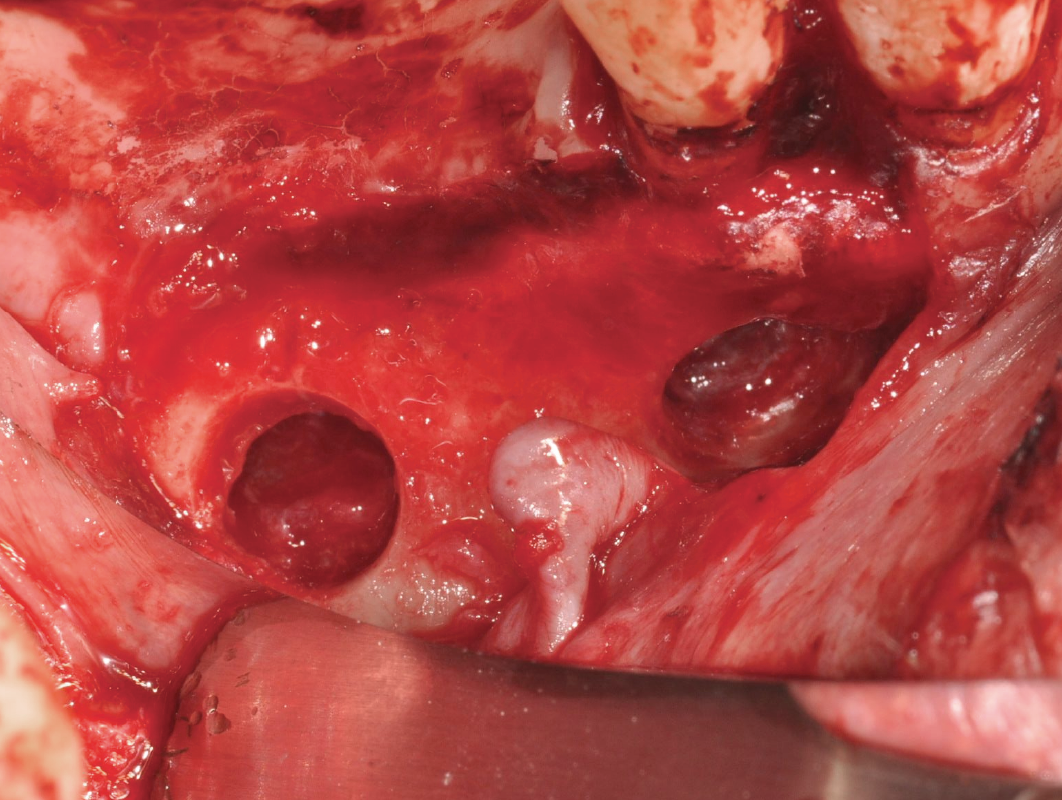

THE TECHNIQUES PIT STOP – MASTERING SINUS AUGMENTATION

Lateral Window Approach – The Formula 1

This approach requires precision, just like a well-timed drift. We’ll break down each step to make your technique smooth and controlled.

Lateral Window Approach – The Formula 1

This approach requires precision, just like a well-timed drift. We’ll break down each step to make your technique smooth and controlled.